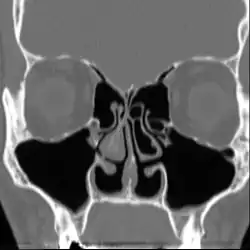

Le syndrome du nez vide (SNV), de l’anglais : Empty Nose Syndrome (ENS), est un état qui apparaît lorsqu'une quantité excessive de tissu nasal producteur de mucus (les cornets ou turbinates en anglais) a été chirurgicalement enlevée du nez ou endommagée, laissant un vide ou des dommages trop importants dans les cavités nasales. Une chirurgie conservatrice peut également mener au syndrome du nez vide car il n'y a pas de standard, ni études, sur la quantité du cornet qui peut être réséquée avant de développer le Syndrome du Nez Vide.

Lorsqu'une quantité excessive des cornets est ôtée ou endommagée, le nez perd ses capacités à convenablement pressuriser, diriger, tempérer, humidifier, filtrer, sentir et détecter le flux d'air inspiré. La synchronisation respiratoire naturelle entre le nez, la bouche et les poumons est également perturbée.

L'évolution naturelle du syndrome du nez vide se fait parfois vers une rhinite atrophique, caractérisée par la dégénérescence du tissu et du cartilage nasal, des cavités nasales évasées et un dysfonctionnement total de la muqueuse nasale restante. Cette rhinite est alors dite « secondaire », car conséquente d'un état préexistant.